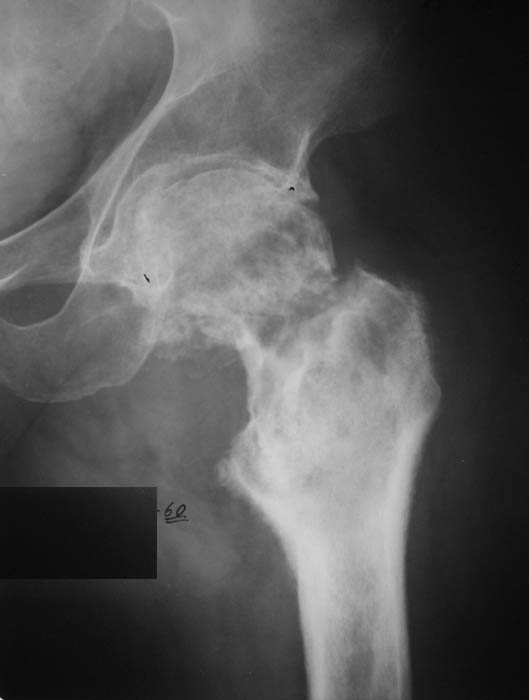

И снова вопрос по эндопротезированию: Пациенту 51 год. Болен с 2000 г, когда отметил умеренные, нараостающие боли в в/3 левого бедра, прогрессирующую контрактуру лев Т/Б сустава.

05.12.04 после падения на бедро боли резко усилились, нога стала неопорной. На рентгенограмме обнаружен патологический перелом шейки бедренной кости. Обследован в отделении костной онкологии. Результат биопсии: асептический некроз проксимального отдела бедренной кости. Вопрос: выбор технологии эндопротезирования - цементная или бесцементная версия. Заранее благодарю! С уважением,А.В.Владзимирский

Про ножку трудно сказать, снимки очень короткие.

Проксимальный отдел бедра не виден достаточно на представленных рентгенограммах; но то, что видно, как раз наводит на мысли о цементной фиксации - цилиндрический канал, измененный calcar, кистозные изменения в области большого вертела и т.д.

Evgueny Tchekashkine 01 Февраль 2005, 04:15

Как то очень подозрительно выглядит проксимальный отдел бедра для такого очень простого гистологического заключения. Вы уверены, что гистология настолько благополучна и в каком варианте она выполнялась: пункционная или открытая с забором костного блока? Не уверен на все сто , но область проксимального отдела бедра - одно из излюбленных мест для гигантоклеточной опухоли, которая зачастую озлакочествляется (имел два подобных наблюдения). Из своей практики могу сказать, что, к сожалению, информативность пункционной биопсии не сравнима с открытой техникой. Поэтому прежде чем решать цементный или бесцементный протез использовать, я бы повторил биопсию в сочетании со сканированием скелета, сывороточная щелочная фосфатаза, кальций, фосфор сыворотки, СОЭ, С- реактивный белок,

Soglasen s Евгений И Чекашкин, proximal Femur does not look right. Sarcoma? Pagets, Osteomyelitis?. Technicality of the implantaion will be dependent upon underlying pathology, and the surgeon's level of comfort.

Действительно, проксимальный отдел бедра выглядит подозрительно. По-моему напоминает болезнь Педжета. Кстати, гистологическое заключение в таком случае часто звучит как "хроническое воспаление", "асептический некроз с элементами лейкоцитарной инфильтрации" и т.п. Далеко не все патоморфологи имеют достаточный опыт для дифференцировки костной патологии.